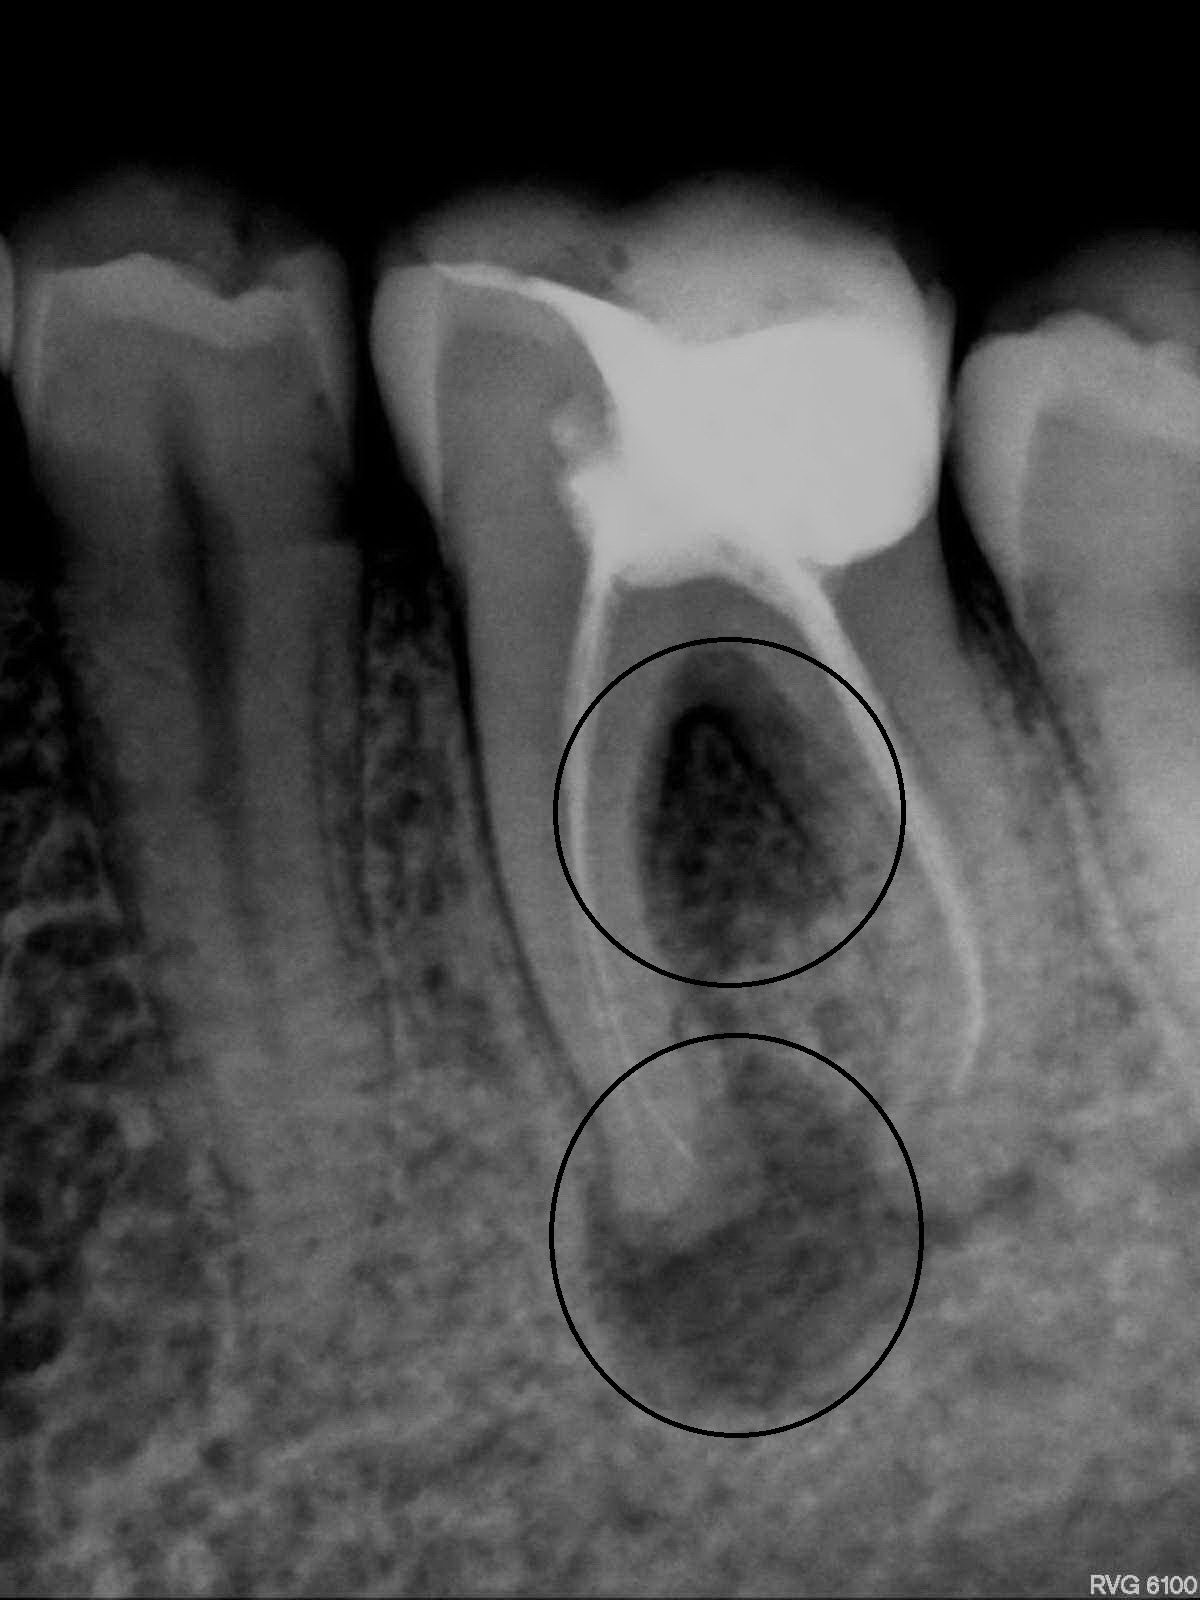

Киста зуба - одно из стоматологических заболеваний воспалительного характера, которое имеет слабую симптоматику, но при этом может закончиться осложнениями.

Киста - это образование около корня зуба. Оно возникает на фоне воспаления, во время которого перед организмом стоит две задачи - уничтожения патогенных клеток и сохранение своих.

киста зубаКогда с последней возникают проблемы и нужно сохранить здоровые окружающие ткани, происходит ограничение воспалительное участка путем формирования полости. Киста - это защитная реакция организма.

Образование кисты может быть результатом травматического проведения корня, попадания инфекции в канал зуба, запущенных заболеваний зубов и корней.